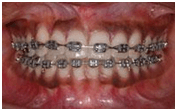

Orthodontic irregularities are generally treated with braces. Braces are usually made from wires and springs attached to tiny metal plates or a plastic mould. Braces apply gentle forces to teeth and encourage them to to move slowly to adopt a different alignment. The best orthodontic results are achieved with children when their teeth are still growing; many adults have orthodontic treatment, but the process takes much longer. Visit our main braces page to read more about how they work and how to look after them.

The orthodontist will assess the teeth that need to be aligned and create either a fixed or removable brace, which can be adjusted during the course of the treatment to achieve the desired effect. The fixed braces, as their name implies, are permanent fixtures and are removed at the end of the treatment period, whereas removable braces can be taken off for eating and cleaning but are generally worn at all other times. Braces will improve the function of the teeth and the general appearance of the person.